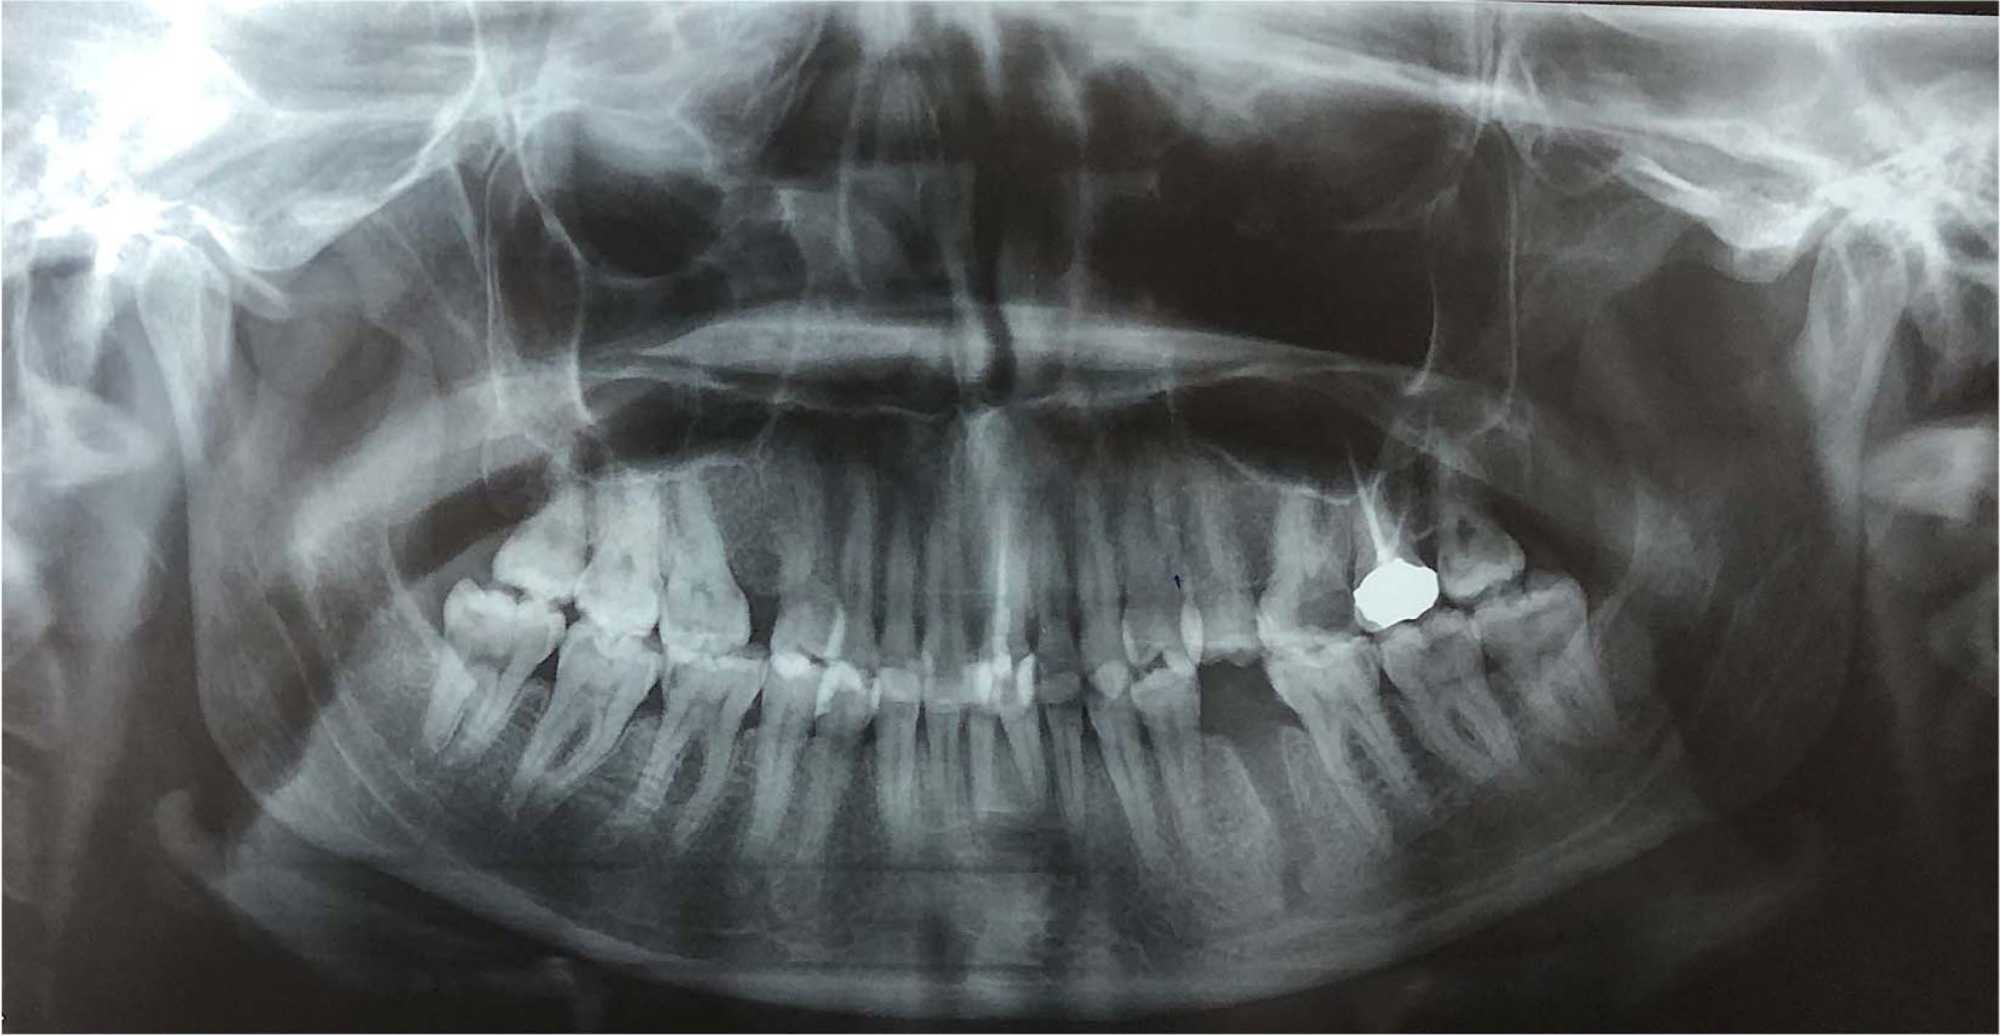

A 30-year-old male patient in good general health was referred for enucleation of a right mandibular inflammatory cyst. Within the first few days postoperatively, he reported numbness in the right extra-oral mandibular area, with no other symptoms.

A panoramic radiograph showed involvement of the IAN within the cystic lesion (Figure 8).

Figure 8. Panoramic radiograph showing the disappearance of IAN canal and its submergence in the radiolucent lesion from tooth 48 to the roots of tooth 43.